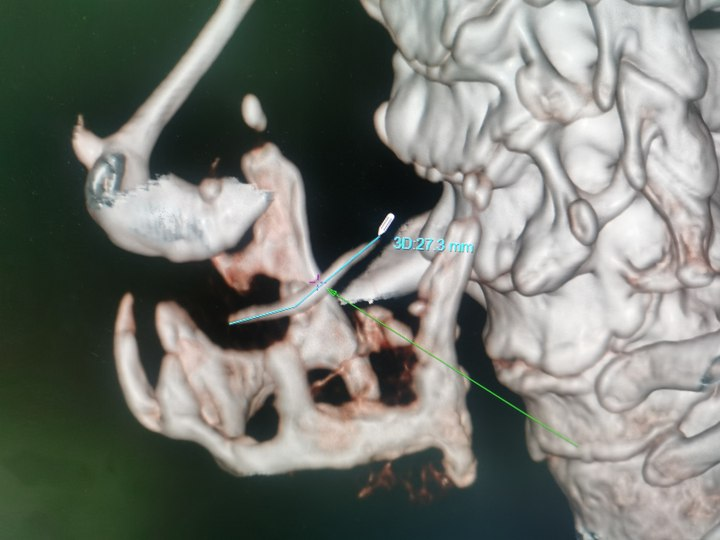

这名73岁的男性患者因误食鱼刺导致咽痛、吞咽困难和声音嘶哑长达三天,并在外院接受抗炎治疗后未见好转,随后紧急转入荆州市中医医院。入院检查发现,鱼刺呈“S”形嵌顿于右侧声门旁间隙,长度约3cm,周围组织严重水肿。此外,患者电子喉镜提示急性会厌炎及声带麻痹,随时可能引发窒息或致命性感染。

面对高龄、基础疾病(高血压)及复杂解剖粘连等风险,耳鼻咽喉头颈外科主任刘燕青带领的团队迅速制定了详细的手术方案。先行食管镜探查定位异物,发现梨状窝黏膜破损,异物被炎性组织紧密包裹,无法以内镜方式安全取出。团队果断转为颈侧入路切开取刺,沿右颈作3.5cm切口,逐层分离颈阔肌、带状肌,切除部分甲状软骨板,暴露声门旁间隙,术中见鱼刺穿透黏膜,团队采用“钝性剥离+分段剪断”策略,分三段取出长约3cm的鱼刺,并进行了穿孔黏膜的缝合修复。术后,患者接受了包括抗感染、抗炎、护胃、雾化、降压、营养支持及中医康复在内的综合治疗。复查时,食管钡餐造影未见造影剂渗漏,患者康复情况良好,已康复出院。